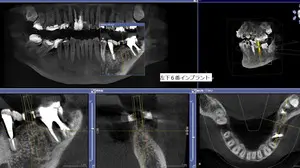

安全性に配慮して、インプラントをCTなどで予定した位置にしっかりと入れる為に

カスタムメイドのマウスピースを綿密に作らせて頂きますので、神経を損傷すると行ったリスクも最大限避けることが可能になっています。